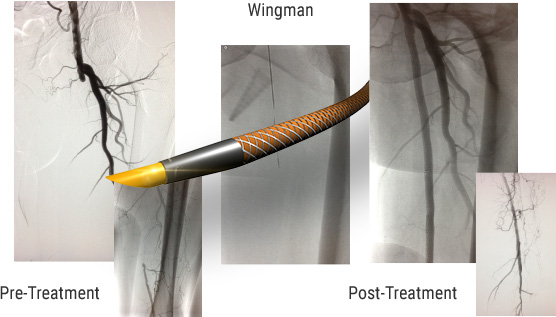

DEVICE: Wingman™

A 77-year-old male presents with a pertinent past medical history of peripheral arterial disease, critical limb-threatening ischemia, paroxysmal atrial fibrillation, type II diabetes, hypertension, hyperlipidemia, and previous smoking.